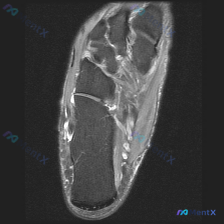

刚看到这个有意思的足部MRI病例,整理了一下影像资料和分析思路,分享给大家一起讨论。 病例影像基础信息 这是一份足部MRI T2序列冠状位图像,切面覆盖足后部到中足的解剖结构,核心观察结果如下: 1. 距下关节区域:关节间隙可见明确线性高信号,符合关节积液表现;关节边缘可见骨质增生(骨赘),局部轮廓...